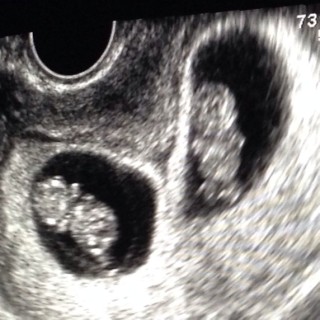

悪阻で大変な毎日。でも元気な二人の心拍が確認出来て私も主人も嬉しかったです。大きさも24.5mmと順調。次回は2週間後。待ちきれない~。